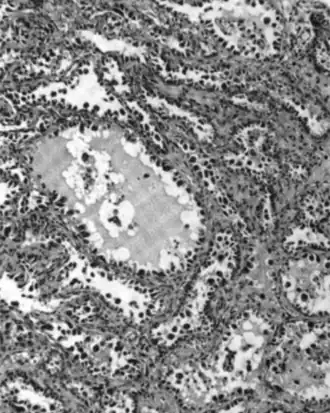

| Micrograph of a mucinous ovarian carcinoma stained by H&E | |

Epithelial carcinoma

Epithelial ovarian cancer typically presents at an advanced stage and is derived from the malignant transformation of the epithelium of the ovarian surface, peritoneum, or fallopian tube.[67] It is the most common cause of gynecologic cancer death.[67] There are various types of epithelial ovarian cancer, including serous tumor, endometrioid tumor, clear-cell tumor, mucinous tumor, and undifferentiated or unclassified tumors.[68] Annually worldwide, 230,000 women will be diagnosed and 150,000 will die.[69] It has a 46% 5 year survival rate after diagnosis because of the advanced stage of the disease at the time of diagnosis.[69] Typically, around 75% of patients are diagnosed as having an advanced stage of the disease because of the asymptomatic nature of its presentation.[69] There is a genomic predisposition to epithelial ovarian cancer and the BRCA1 and BRCA2 genes have been found to be the causative genes in 65–75% of hereditary epithelial ovarian cancer.[69]

Mucinous adenocarcinoma

Mucinous adenocarcinomas make up 5–10% of epithelial ovarian cancers. Histologically, they are similar to intestinal or cervical adenocarcinomas and are often actually metastases of appendiceal or colon cancers. Advanced mucinous adenocarcinomas have a poor prognosis, generally worse than serous tumors, and are often resistant to platinum chemotherapy, though they are rare.[29]